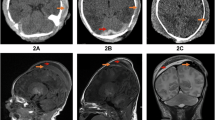

Tschauner S, Sorantin E. Imaging After Birth Trauma and in Suspected Non-accidental or Inflicted Injury. Springer, Cham; 2023.

Acuna J, Adhikari S. Point-of-care Ultrasound to distinguish subgaleal and Cephalohematoma: Case report. Clin Pr Cases Emerg Med. 2021;2:198–201.

Sorokan ST, Jefferies AL, Miller SP. Imaging the term neonatal brain. Paediatr Child Health. 2018;23:322–8.